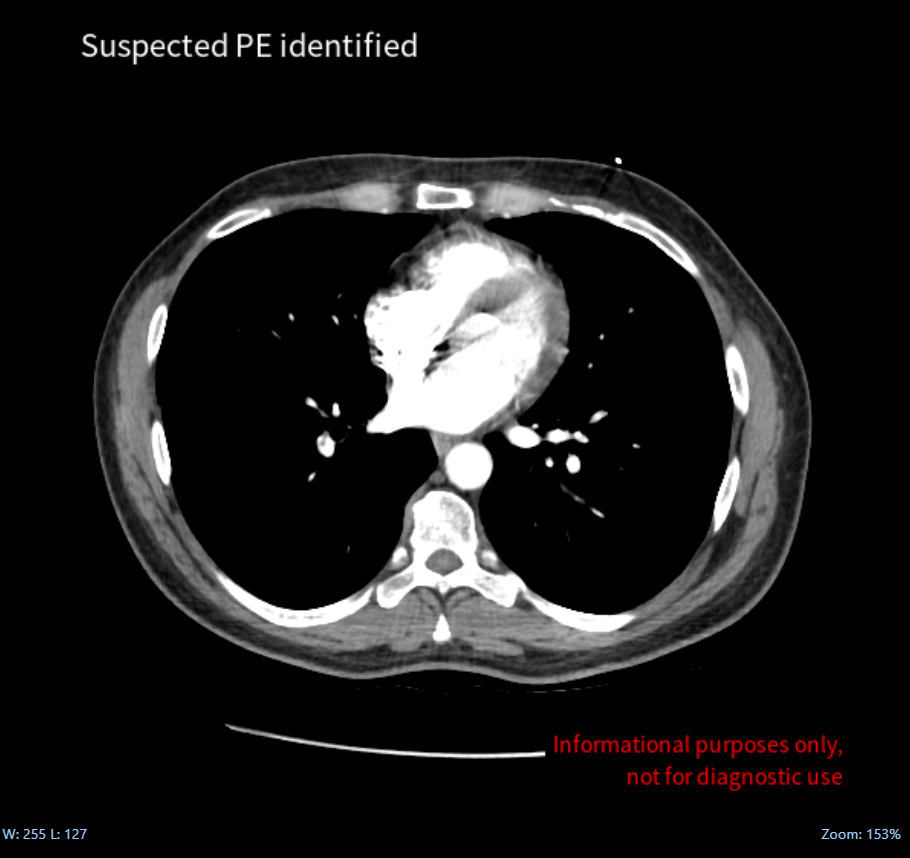

In response to this critical issue, Avicenna.AI developed CINA-PE, a cutting-edge solution that swiftly and automatically detects pulmonary embolism from chest CT Scan.

Picture a tool that empowers healthcare professionals to streamline the management of pulmonary embolism patients. This case study, ‘How to Optimize Management of Pulmonary Embolism Patients?’, demonstrates how AI technology supports radiologists in rapidly identifying critical findings, aiding swift, informed decisions to improve patient care and outcomes in urgent scenarios.